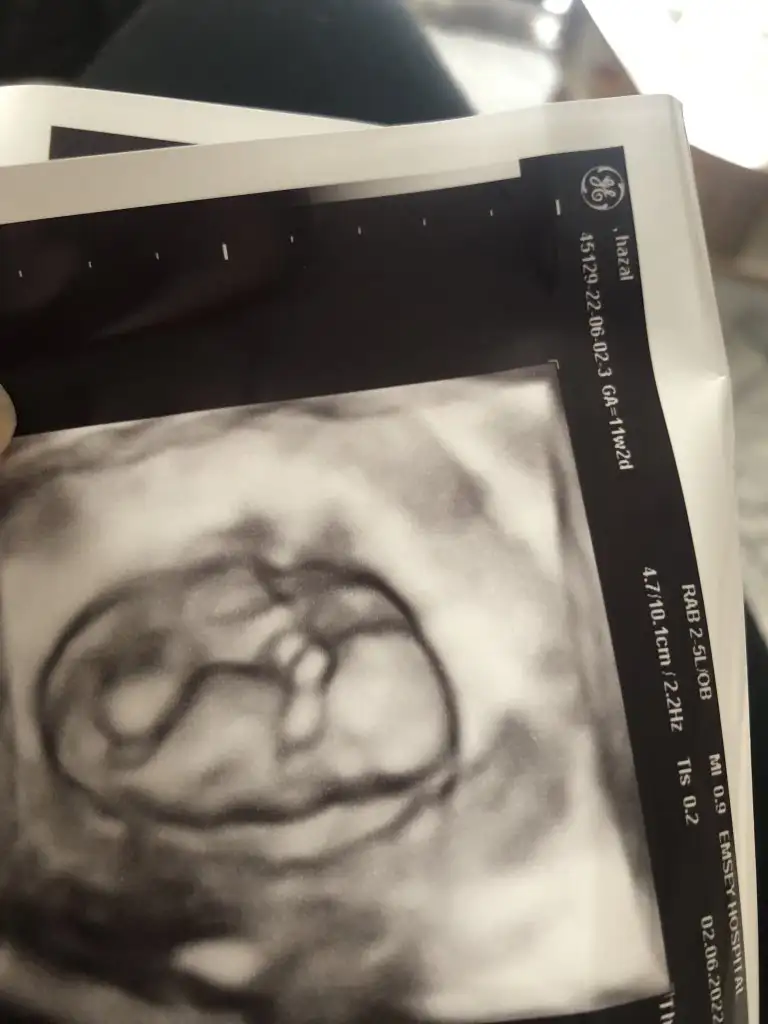

Merhaba nursu 11 haftalik atmistim prenses gibi demistin bugün 13 +2 hafta olduk özel hastanede doktor %90 erkek dedi son foto attım yeniden baksana

12+5 günlük karından çekildi yorum yapabilirmisiin Pasha22 Pasha22